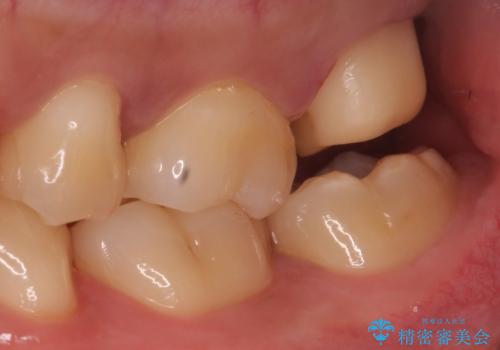

- 銀の詰め物のやり替えを主訴に来院されました。

歯の奥が歯ぐきに埋もれている状態であったため、埋まっている親知らずを抜歯しつつ歯茎の高さを落とし、外れにくいジルコニアクラウンを装着していきます。

歯のみでなく歯茎の調整も行うことで、外れにくい被せ物を装着することが可能になります。